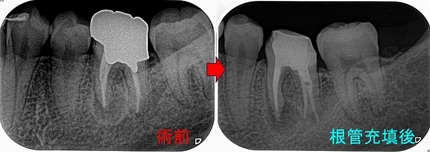

今回のケースは12歳の男の子

7ヵ月前に治療を行ったが、1ヵ月前から痛みが出てきた。

10日前に温水痛とズキズキする自発痛が出てきて3日で落ち着いた。

とのこと

この痛みから予想できるのは、神経が死んで痛みが止ったケースが多いです。

レントゲン

2025EEdental URI (1).jpg

第一大臼歯に根尖病変が見られ、やはり神経が死んでおり根管治療が必要なケースとなっていました。

術前

2025EEdental URI (4).jpg

咬合面と口蓋側にレジン充填がしてあります。

保護者の方に根管治療が必要な事、この年齢なので大きく削らず(被せ物ではない方法)3mmぐらい穴を開けてそこから治療することを説明

治療1回目

詰めてあるレジンを顕微鏡下で外すと、過去の治療で小さな露髄(0.3mm程度)をしていたようで、

神経からは出血はなくやはり神経は死んでいるよう。

ここから髄角部分を取っていくのですが、やはり若いだけあって髄角の張り出しが大きく

何度もう蝕検知液(染め出し液)を使いながらチェック&切削の繰り返し

髄角をきちんと処理して4根管の穿通・拡大・洗浄

2025EEdental URI (2).jpg

入り口はなるべく削らず中をくり抜く(凄く手間はかかります)

治療2回目(白っぽい所が仮蓋 ヨードで消毒しています)

2025EEdental URI (6).jpg

症状のないことを確認して根管充填+レジンコア+レジン充填

2025EEdental URI (3).jpg

口蓋根は根尖が大きく開いていた為MTAセメントを使用

MB,MB2,DBはガッタパーチャー使用

術後

2025EEdental URI (5).jpg

3mmちょっとの穴から治療を終えました。

歯髄腔が石灰化だらけのケースも難易度高いですが、歯髄腔が広いケースも小さな穴から髄角を処置するもの難易度高いですね。

この後、経過観察をして行きます。

若い時の根管治療はきちんとやっておかれた方がいいと思います。